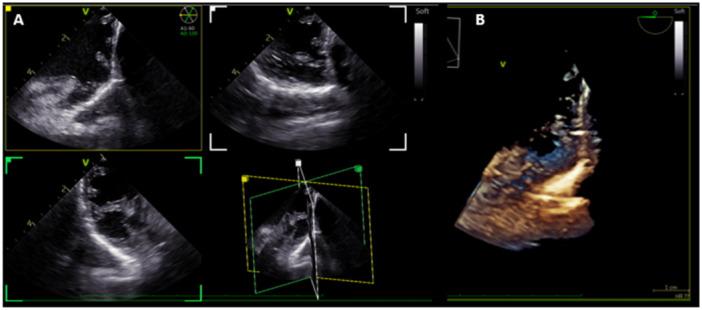

Intracardiac echocardiography (ICE) is an essential imaging modality for electrophysiology procedures, allowing intraprocedural monitoring, real-time catheter manipulation guidance, and visualization of complex anatomic structures. Four-dimentional (4D) ICE is the next stage in the evolution of the technology, permitting 360° rotation of the imaging plane, simultaneous multiplanar imaging, and volumetric acquisition, similar to transesophageal echocardiography (TEE). In this study, we report our experience with a novel 4D ICE catheter (NuVision, Biosense Webster) in structural electrophysiology procedures and difficult ventricular ablations in a swine preclinical model.

METHODS

7 Yorkshire swine underwent 4D ICE (NuVision, Biosense Webster) imaging procedures and anatomical shells of the RV, LV, and LA were created on the CARTO mapping system. Ablation was performed on the RV moderator band and LV papillary muscles under imaging guidance with the 4D ICE catheter. Additional ICE images were obtained of the LAA to simulate placement of a left atrial appendage occlusion (LAAO) device. Triphenyl tetrazolium chloride was administered before euthanasia and hearts were harvested, fixed in formalin, and sectioned.

RESULTS

CARTOSOUND reconstruction was completed using the novel multiplane imaging software platform, allowing for creation of anatomy with minimal movement of the ICE catheter. Maps generated were similar to 3D reconstruction acquired in pre-procedure CT. Ablation lesions were successfully delivered to the LV papillary muscles and RV moderator band with excellent correlation between gross pathology, electroanatomic mapping (EAM), and ICE images. 2D, multiplane, and 3D volumetric images were obtained of the LAA with minimal catheter movement to simulate use for an LAAO procedure.

心腔内超声心动图(ICE)是电生理手术中必不可少的成像方式,可进行术中监测、实时导管操作引导以及观察复杂的解剖结构。四维(4D)ICE是该技术发展的下一阶段,它允许成像平面进行360°旋转、同时进行多平面成像以及容积采集,类似于经食管超声心动图(TEE)。在本研究中,我们报告了在猪临床前模型中使用新型4D ICE导管(NuVision,Biosense Webster)进行结构电生理手术和困难心室消融的经验。

方法

7只约克夏猪接受了4D ICE(NuVision,Biosense Webster)成像手术,并在CARTO标测系统上创建了右心室、左心室和左心房的解剖模型。在4D ICE导管的成像引导下,对右心室节制索和左心室乳头肌进行消融。获取了额外的左心耳ICE图像以模拟左心耳封堵(LAAO)装置的放置。在安乐死之前给予三苯基四氮唑氯化物,然后取出心脏,用福尔马林固定并切片。

结果

使用新型多平面成像软件平台完成了CARTOSOUND重建,在ICE导管移动最小的情况下创建了解剖模型。生成的图谱与术前CT获得的三维重建图谱相似。成功地将消融灶传递至左心室乳头肌和右心室节制索,大体病理学、电解剖标测(EAM)和ICE图像之间具有良好的相关性。通过最小的导管移动获取了左心耳的二维、多平面和三维容积图像,以模拟用于LAAO手术。